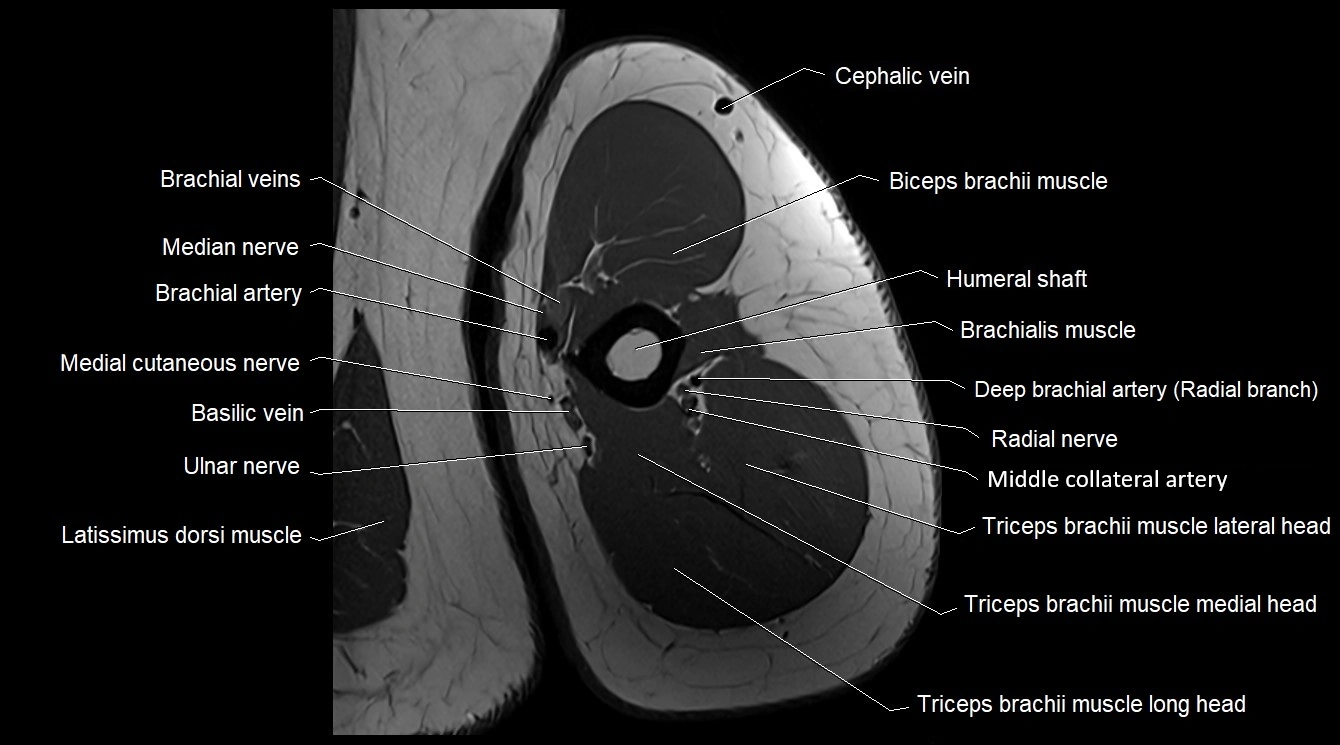

- Biceps brachii muscle

- Brachial artery

- Brachialis muscle

- Cephalic vein

- Lateral head of triceps brachii muscle

- Latissimus dorsi tendon

- Long head of triceps brachii muscle

- Medial cutaneous nerve of forearm

- Medial head of triceps brachii muscle

- Median nerve

- Middle collateral artery

- Radial nerve

- Triceps brachii muscle